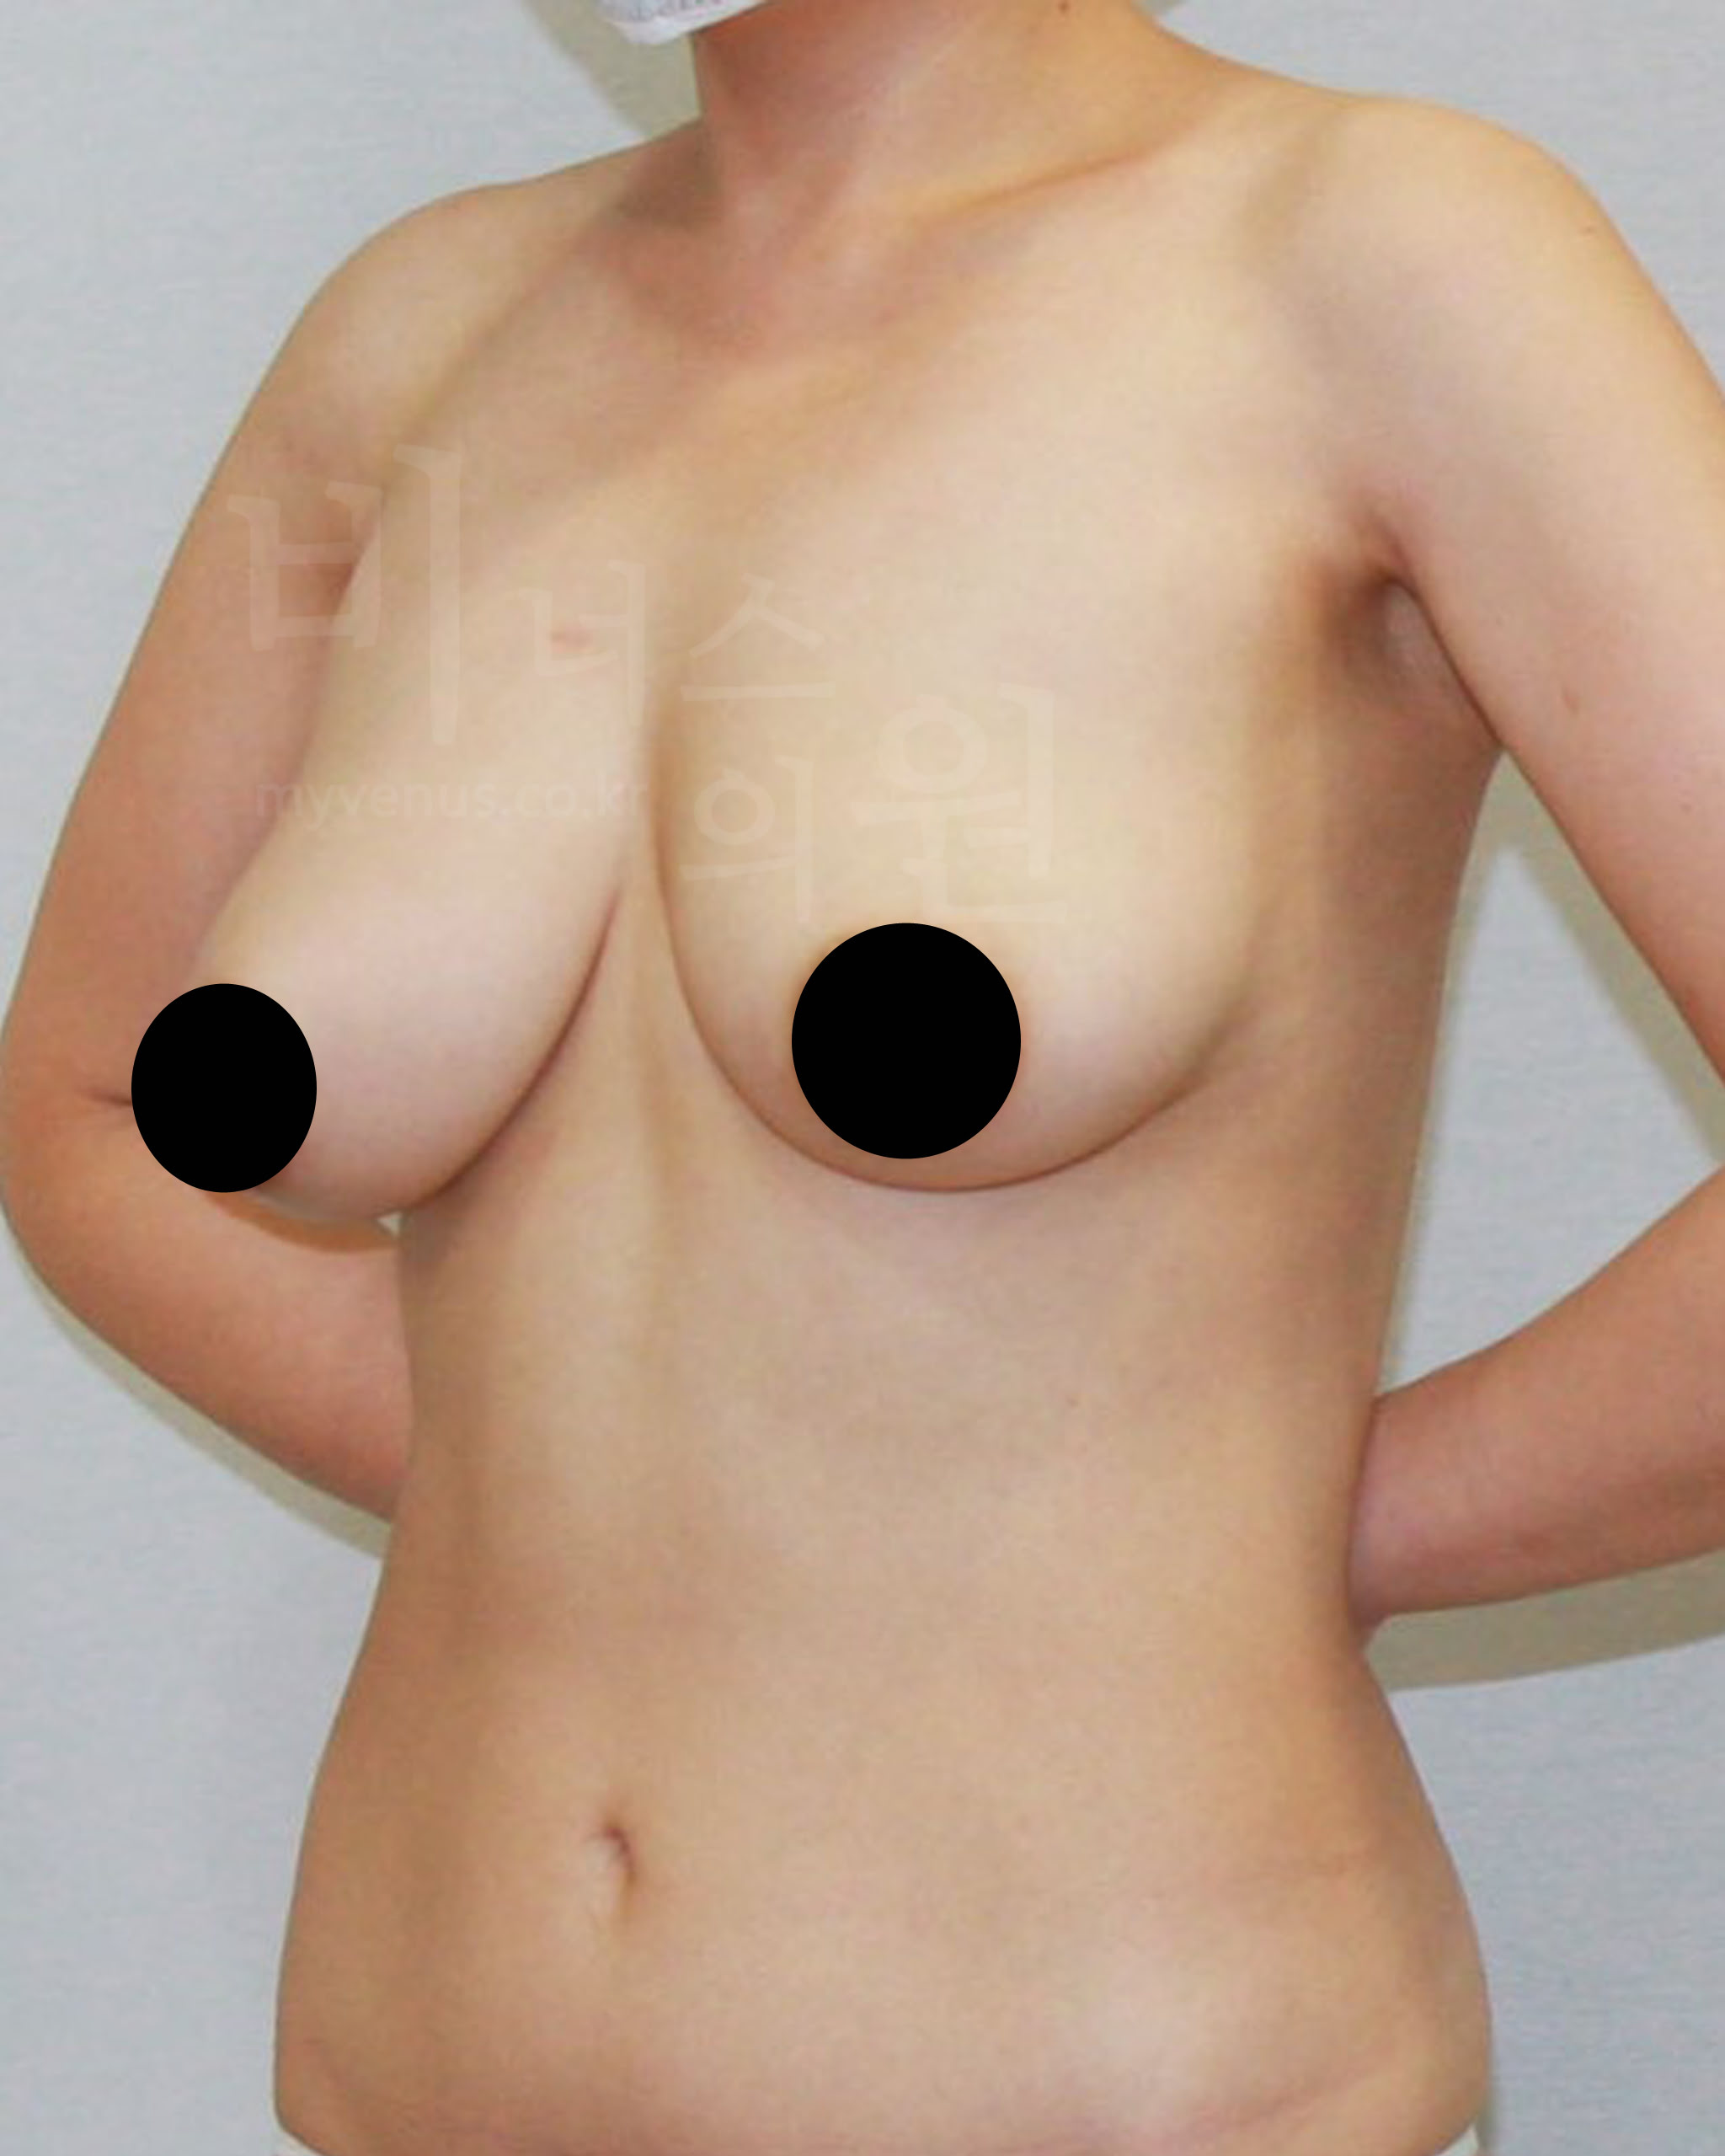

가슴축소 지방흡입 전 사진

유방이 처지고 몸에 비해 큰 가슴 모습

가슴축소 지방흡입 후 사진

처짐 없이 사이즈가 감소와 리프팅 된 모습

젊은 여성분으로 무겁고 처진 가슴의 사이즈 감소를 위해 내원해 주셨어요. 가슴축소 지방흡입 후 가슴 사이즈가 주었으며, 처짐 없이 볼륨 업 된 가슴을 확인할 수 있어요. 가슴뿐만 아니라 부유방, 겨드랑이, 유방 옆구리 지방흡입을 함께 함으로써 주변 부위와 어색함 없어요.